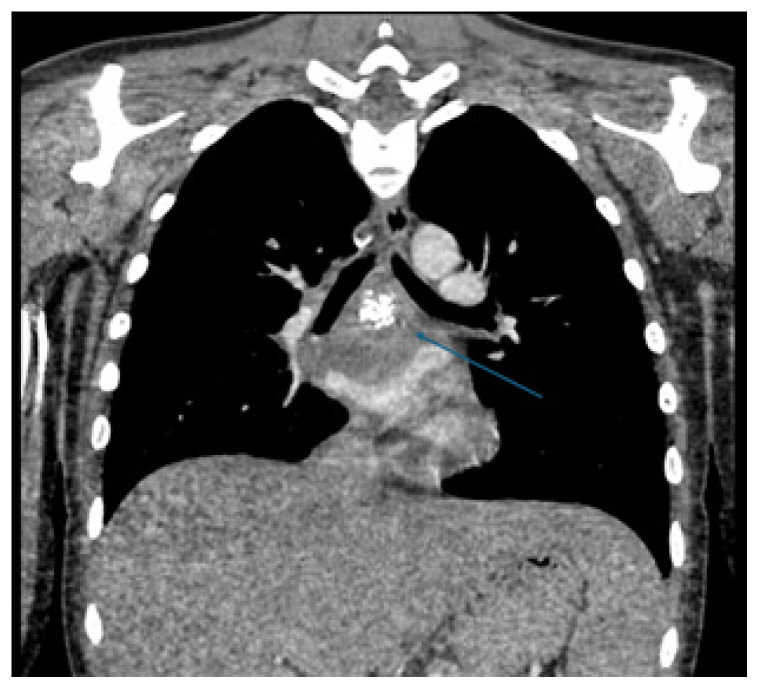

A Case Report of a Mediastinal Granuloma Related to Histoplasmosis with Streptococcus dysgalactiae Subspecies equisimilis Superinfection Resulting in Abscess and Subsequent Pericarditis in a Pediatric Patient.

Abstract Image